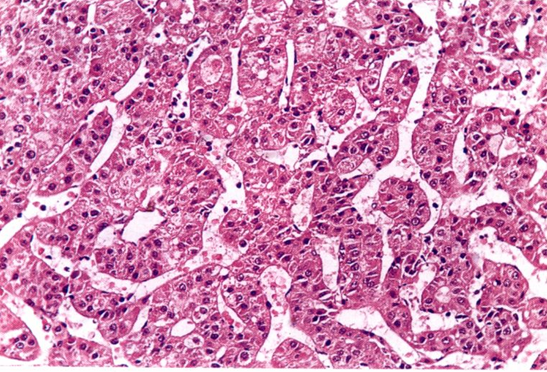

(1)肝细胞癌:由肝细胞发生的癌肿,最多见(90%)。

分化好→癌细胞多角形,核大,有丰富的血窦,分泌胆汁,间质少。

分化差→异型性明显,有瘤巨细胞。